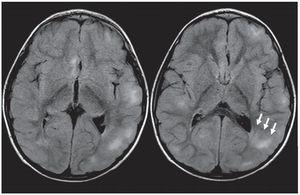

Su tamaño es variable. Mientras las pequeñas son lesiones de tipo puntiforme, hiperintensas en ponderación T2 y FLAIR, las grandes presentan diversos aspectos: pueden ser lineales, tener forma de cuñas o integrar un conglomerado. Sin embargo, la presentación más habitual es el patrón lineal, que se extiende desde la región periventricular hasta la corteza y se denomina «líneas de migración radial».

En la TC pueden ser levemente hipodensas y también suelen calcificarse (fig. 6), mientras que en la RM se identifican como imágenes hiperintensas en ponderación T2 y FLAIR (figs. 7 y 8). Rara vez realzan poscontraste.

Figura 7. Líneas de migración radial. Secuencia FLAIR donde se observa, a nivel de la sustancia blanca periventricular adyacente a la prolongación occipital del ventrículo lateral izquierdo, una línea hiperintensa que se extiende hacia la corteza (flechas rectas). También se presentan quistes parenquimatosos (flechas curvas). Ambos hallazgos son característicos de esclerosis tuberosa.

Figura 8. Lesión de sustancia blanca. En la secuencia FLAIR se nota una banda gruesa hiperintensa que se extiende desde la sustancia blanca periventricular hasta la corteza (flechas).